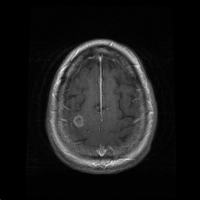

Los especialistas explican que en vez de utilizar una solución salina o agua estéril para la irrigación, la mujer utilizó agua del grifo, donde habitaban los organismos nocivos.